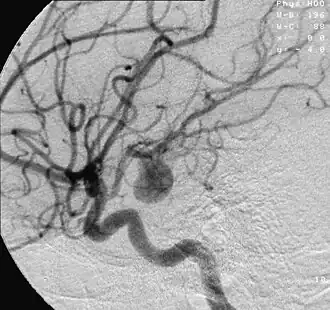

Un anévrisme ou anévrysme (du mot grec ancien « ἀνεύρυσμα » [aneúrusma] signifiant « dilatation », dérivé du verbe « ἀνευρύνω » [aneurúnô] signifiant « élargir, dilater ») est une dilatation localisée de la paroi d'une artère aboutissant à la formation d'une poche de taille variable, communiquant avec l'artère au moyen d'une zone rétrécie que l'on nomme le « collet ». Sa forme habituelle est celle d'un sac, son diamètre pouvant atteindre plusieurs centimètres.

Avec le temps, l'anévrisme augmente progressivement de diamètre, et comme la tension de la paroi artérielle est proportionnelle au rayon de l'artère (conséquence de la loi de Laplace), le risque de rupture augmente[1]. Le risque de rupture devient menaçant dès un diamètre de 7 mm (pour les anévrismes des artères cérébrales). Lorsqu'il se rompt, l'anévrisme entraîne une hémorragie interne pouvant, si la rupture est importante, rapidement entraîner la mort par compression d'organes vitaux (le cerveau pour les localisations cérébrales, le cœur pour les localisations dans la crosse de l'aorte).

Les anévrismes sont particulièrement fréquents au niveau des artères cérébrales, où leur rupture entraîne une hémorragie méningée (qui est un accident vasculaire cérébral).

Anévrismes intracrâniens

Leur rupture provoque un accident vasculaire cérébral souvent grave.